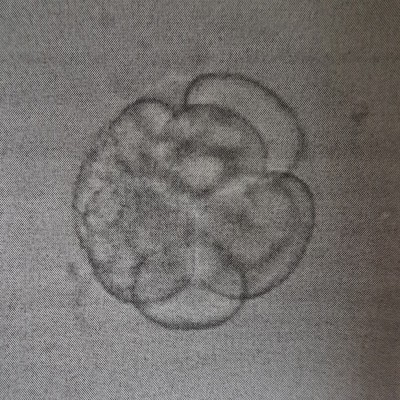

können Sie mir etwas zur Qualität unseres Embryos sagen, Transfer war an PU+2. Das Labor machte uns keine große Hoffnung aufgrund des Grades an Fragmentierung.

Bitte um Beurteilung